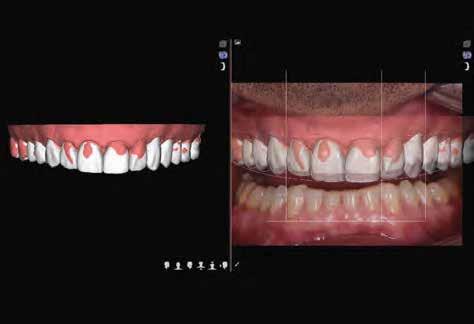

Az orális szkennerek és a szoftveres háttér utóbbi években bekövetkezett fejlődésének köszönhetően egyre több fogászati munkafolyamat területén figyelhetjük meg a digitalizáció térnyerését. Ennek a fejlődésnek köszönhetően jelentős mértékben javult a fogorvos-fogtechnikus közötti kommunikáció hatékonysága. A digitális mosolytervezés (Digital Smile Design, DSD) egy olyan virtuális eszköz, amely segítségével megtervezhetjük az arc szimmetrikus és esztétikus megjelenése helyreállításának a menetét. Ez a módszer nem csak a különböző szakterületek képviselői közti kommunikációt javítja,

hanem lehetővé teszi, hogy összességében lényegesen jobb végeredményt érjünk el a rehabilitáció során. A mosolytervezés dokumentációja fontos lépés, akár a 2D-s, akár a 3D-s tervezésről van szó, valamint ennek jelentős szerepe van a rehabilitáció kimenetelének szempontjából is. Ezt a folyamatot akár teljesen digitális módszerekkel is el lehet végezni. A mozgóképpel történő dokumentáció előnye abban rejlik, hogy így sokkal egyszerűbbé válik a kiindulási állapot dokumentációja, a mosolytervezés, az arc szimmetriájának kiértékelése, a kezelési terv elkészítése, továbbá hatékonyabbá lehet tenni a fogorvosi team-en belüli kommunikációt és a páciens bekapcsolását a folyamatba.

Ebben a cikkben egy olyan esetet ismertetünk, ahol a kezelés során alkalmazott munkafolyamatokat digitálisan végeztük el. Minimál-invazív preparációt követően – digitális mosolytervezés alapján – lithium-diszilikát tömbökből monolitikus héjakat és koronákat készítettünk CAD/CAM technológia felhasználásának segítségével. Az elkészült restaurátumok segítségével helyreállítottuk az elvesztett harapási magasságot, valamint megszüntettük az ebből adódó esztétikai hátrányokat és az emiatt kialakult temporomandibuláris ízületi diszfunkciót.

A már előzetesen preparált felső frontfogak csiszolt csonkjainak megtartottuk az eredeti formáját. Az alsó és felső őrlőfogak preparációja nem volt szükséges (1.7-1.4, 2.4-2.7, 3.7-3.4, 4.4-4.7), az alsó kismetsző fogakat minimál invazív módon készítettük elő. Az előkészítést követően új digitális lenyomat készült. Az így kapott digitális adatokat továbbítottuk a fogtechnikai laboratóriumba (9. ábra). A virtuális modellt ezek alapján hozták létre (AnatomicLab), és a minta elkészítéséhez szükséges STL fájlt továbbították egy háromdimenziós nyomtatóra (SolFlex 650, VOCO), amely segítségével elkészítették az új mintát (V-Print model, VOCO).